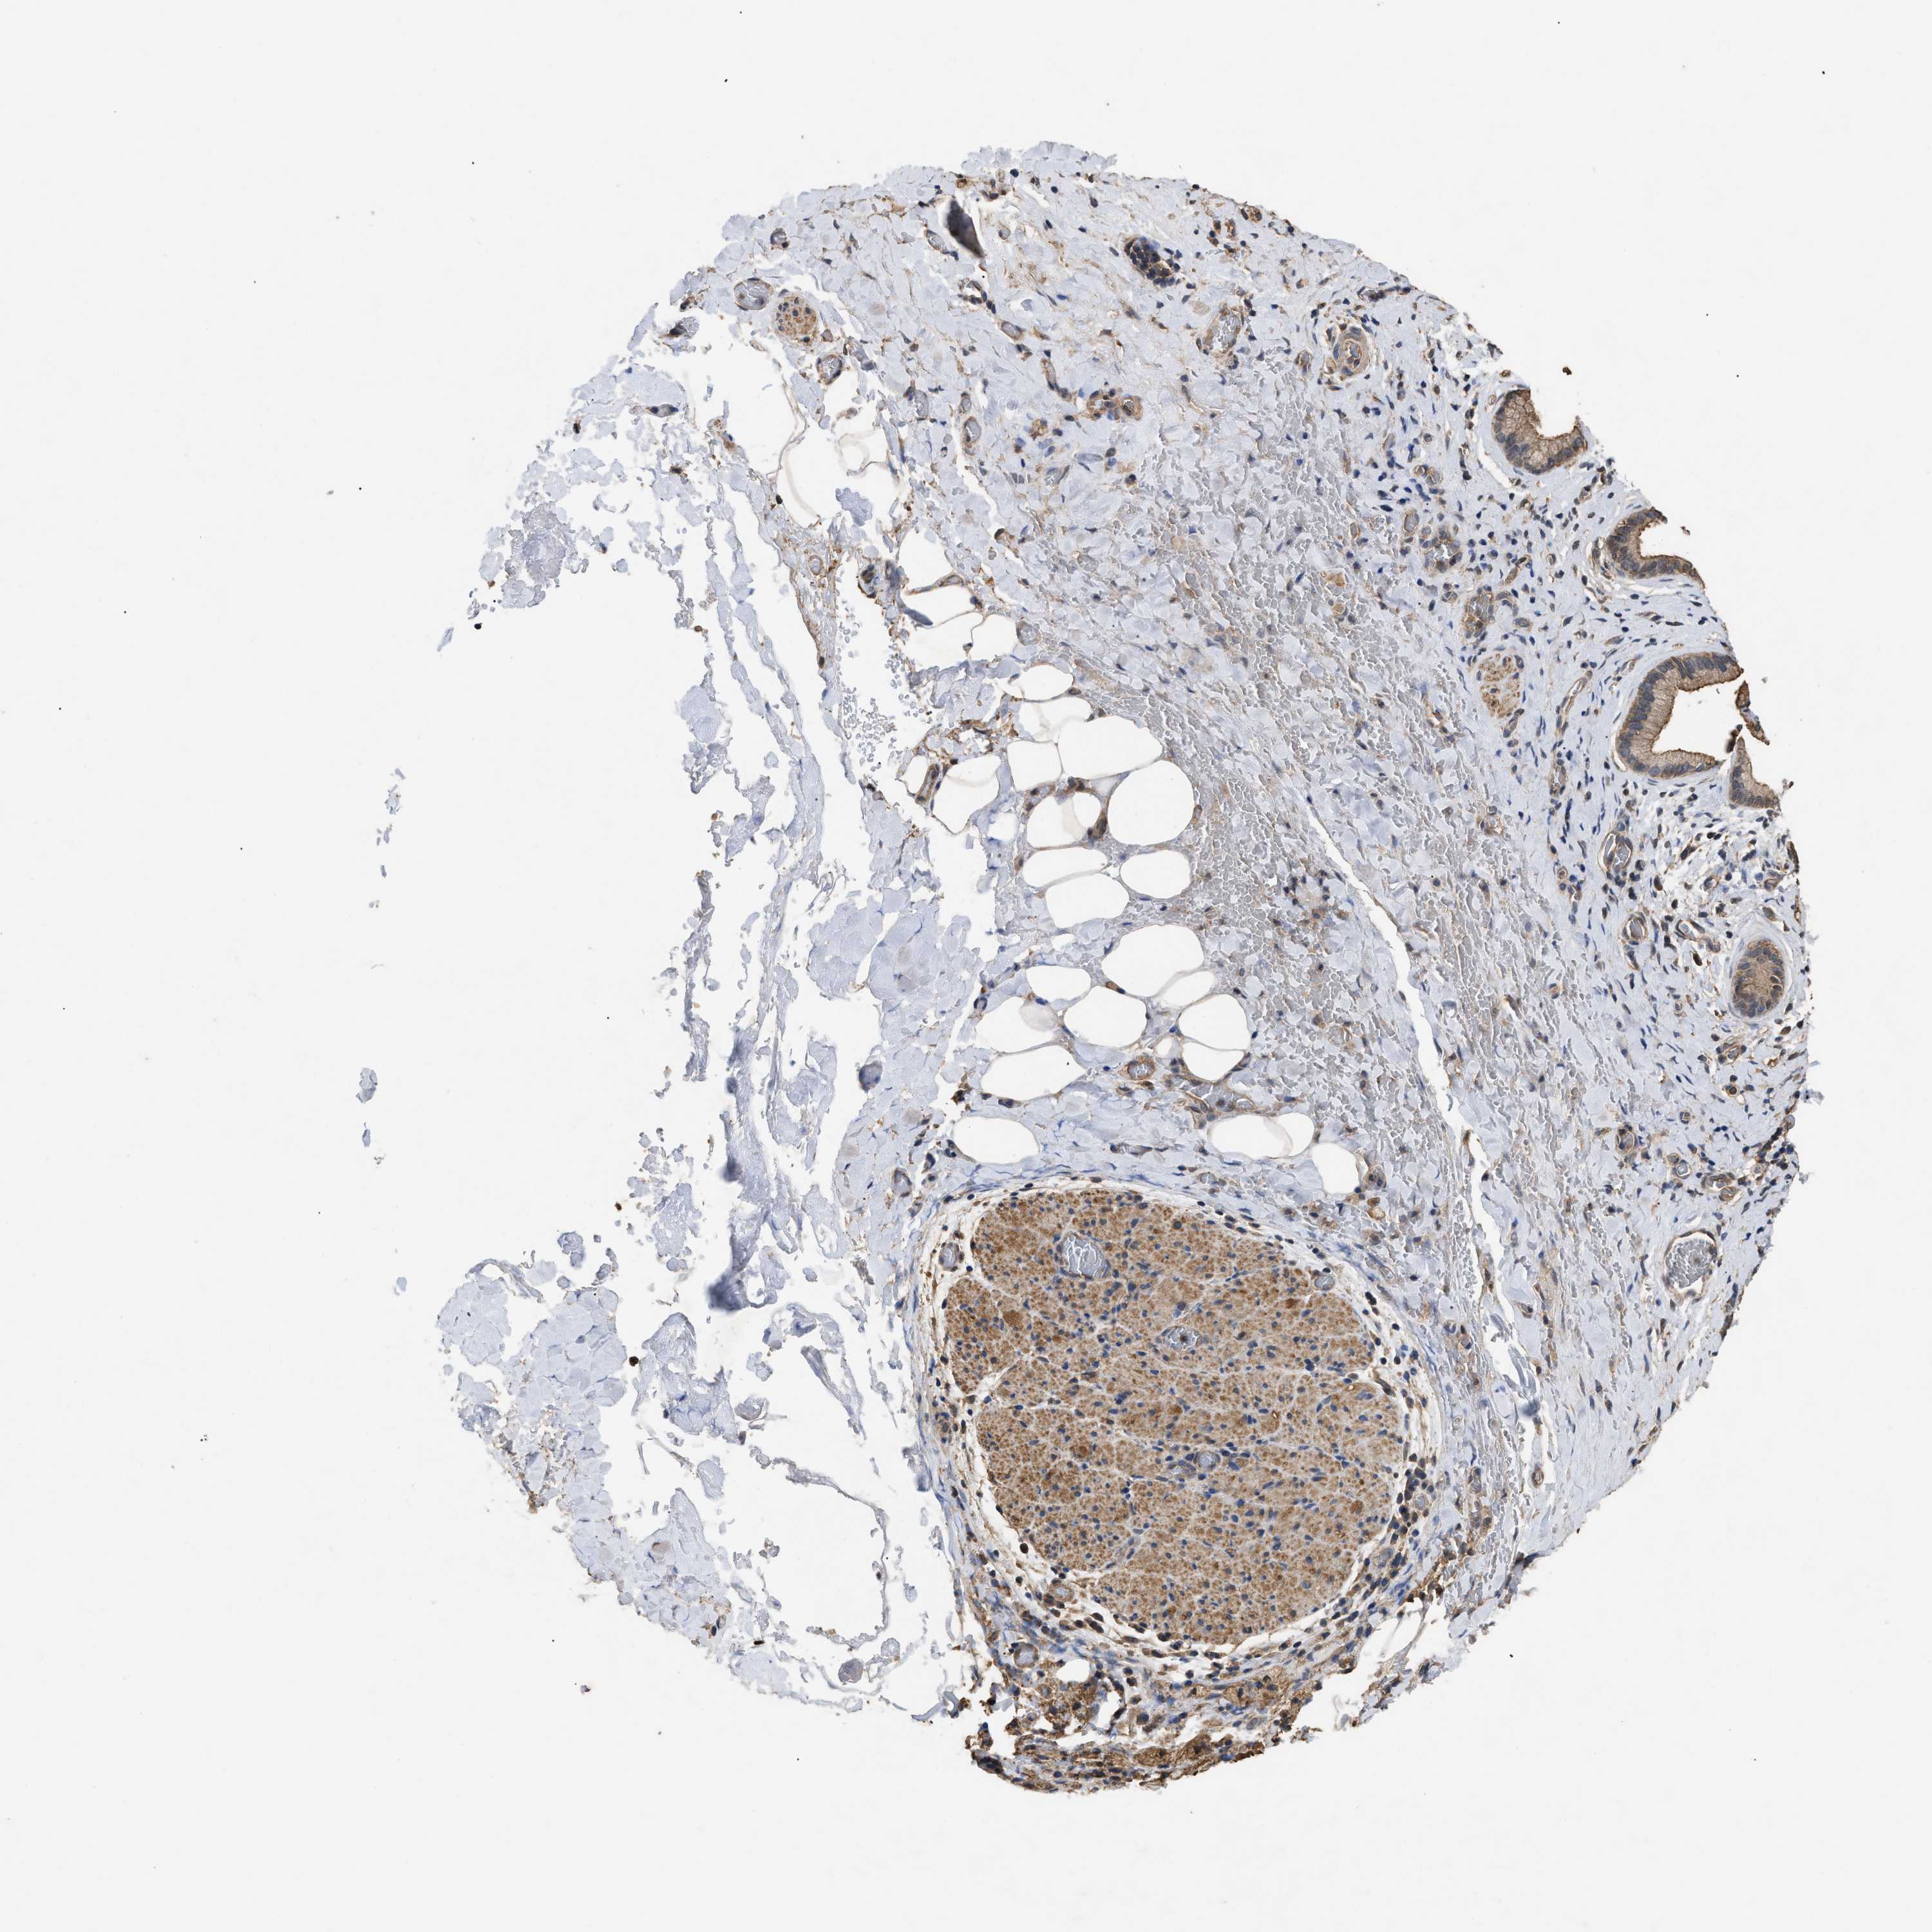

LIVER CANCER - Protein expressioni

A mouse-over function shows sample information and annotation data. Click on an image to view it in a full screen mode. Samples can be filtered based on level of antibody staining by selecting one or several of the following categories: high, medium, low and not detected. The assay and annotation is described here.

Note that samples used for immunohistochemistry by the Human Protein Atlas do not correspond to samples in the TCGA dataset.

Antibody stainingi

Antibody staining in the annotated cell types in the current human tissue is reported as not detected, low, medium, or high, based on conventional immunohistochemistry profiling in selected tissues. This score is based on the combination of the staining intensity and fraction of stained cells.

Each image is clickable and will lead to virtual microscopy that enables deeper exploration of all samples and also displays staining intensity scores, fraction scores and subcellular localization as well as patient and tissue information for each sample.

Antibody HPA044999

Antibody CAB018558

Staining

High

Medium

Low

Not detected

Intensity

Strong

Moderate

Weak

Negative

Quantity

>75%

75%-25%

<25%

None

Location

Nuclear

Cytoplasmic/membranous

Cytoplasmic/membranous,nuclear

Cholangiocarcinoma

Carcinoma, Hepatocellular, NOS